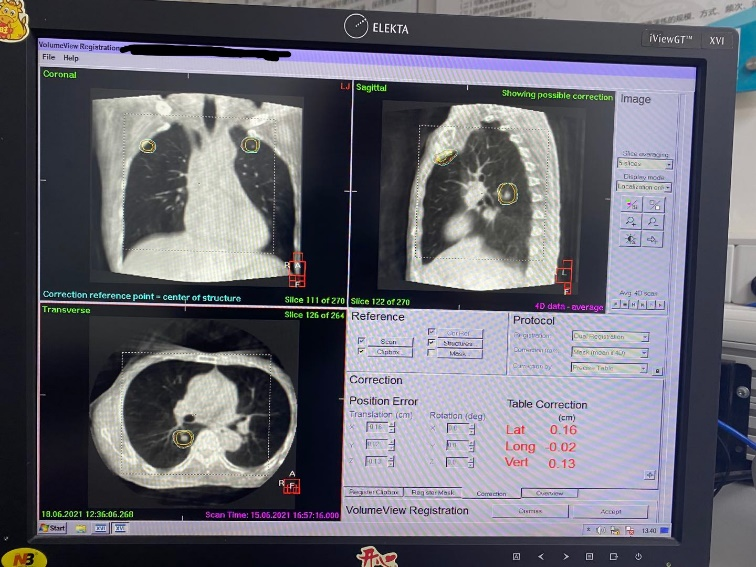

胸部原发恶性肿瘤约占全部恶性肿瘤的三分之一,而肺转移也是恶性肿瘤最常见的转移部位之一。作为运动器官,双肺多发病灶在国内外都是放疗的难点。本次研讨会分别从肺部4D影像引导定位技术和在线分次内4D影像引导高精动态放射外科技术两方面着手,我院放疗科专家组利用医科达Versa HD™的HDRS高精动态放射外科技术等先进软硬件技术成功攻克了难题,成功为两位双肺多发转移的晚期疑难病例(双肺转移灶分别为5个和6个)实施在线分次内四维图像引导的精准SBRT放射治疗。

此次实时在线影像引导功能和高精动态放射外科技术对两位患者进行精准放疗,做到了对肿瘤放疗的精、准、狠、快,将传统放疗技术不可能解决的问题变成了现实,属于广西区内首创、处于国内外领先水平。